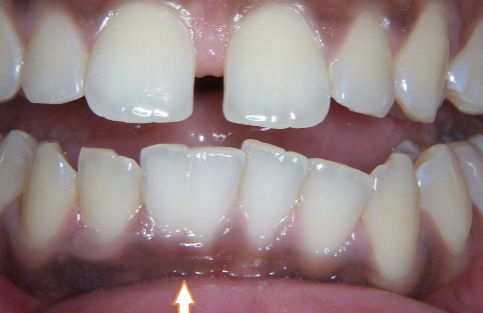

a hereditary condition of dentin in the absence of any systemic disease (opalescent dentin), AD, genetic mutation is DIFFERENT from osteogenesis imperfecta

dentinogenesis imperfects (DGI)

DGI-II clinical presentation

isolated opalescent teeth, most common

affects both dentition, steel-grey/ translucent/ opalescent crowns, brittle enamel

DGI

DGI radiographic presentation

bulbous crown, cervical constriction, pulp obliteration varies, expanded pulp = shell teeth